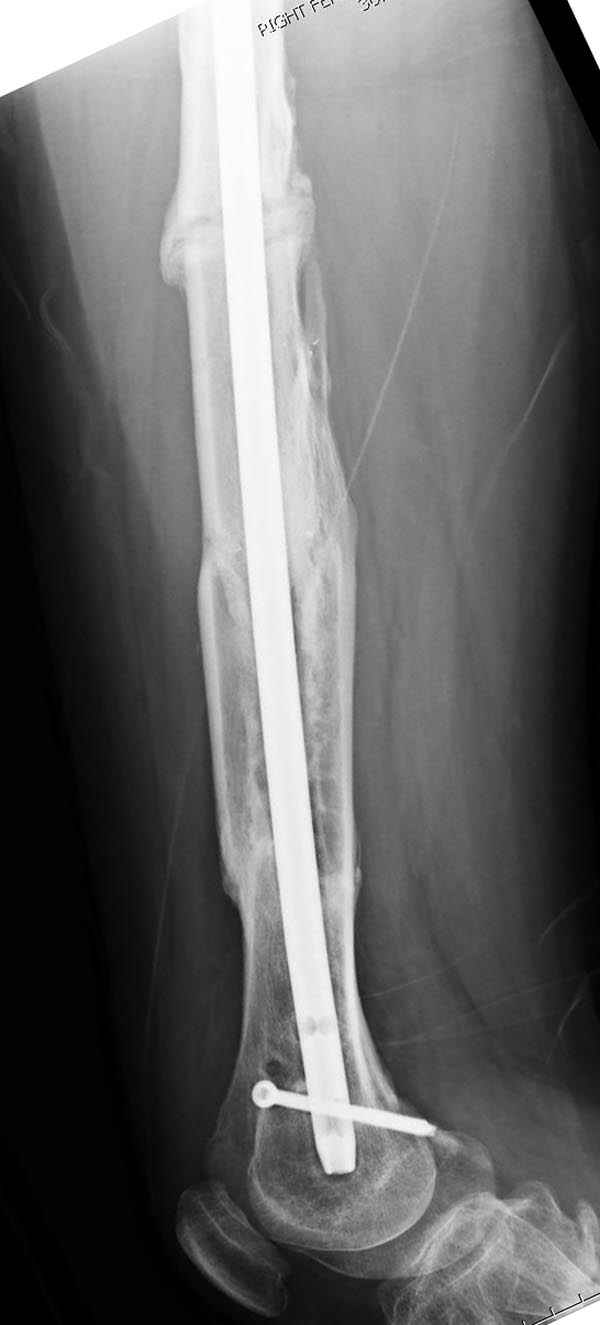

Рутинный интрамедуллярный остеосинтез с расверливанием и с фиксацией реконструктивным трокантерик штифтом (рис №1, №2),

если первые 4 месяца послеоперационного периода проходил без проблем, но на 5 месяце появились боли в дистальном отделе бедра и температура, т.е. симптомы медуллярного инфицирования (рис №3, №4).

и последующих снимках (рис №10, 11, 12, 13) перелом сростается и передвигается с полной нагрузкой.

При обзоре причин перелома, на снимке №2 обнаружили, что один из стержней аппарата наружной фиксации проходил только через передний кортекальный слой, что создало стрессовую зону на бедре и в результате перелом из-за незначительной травмы.